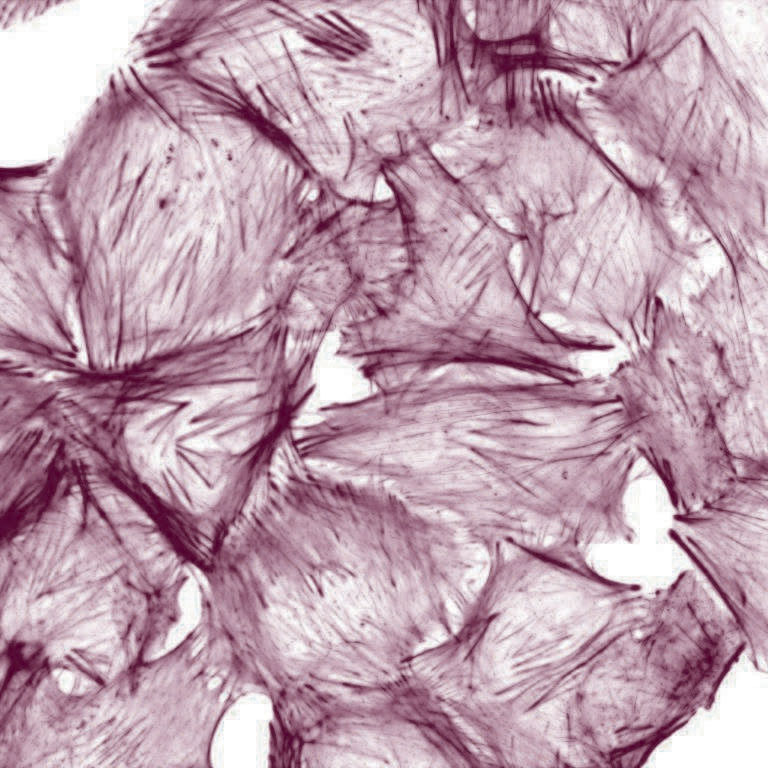

Opis:Zdjęcie przedstawia komórki T24 (nowotwór ludzkiego pęcherza moczowego) ze strukturami cytoszkieletu, które zostały fluorescencyjnie oznaczone (kolor zielony: aktyna F). Zdjęcie wykonano fluorescencyjnym mikroskopem konfokalnym ; Praca nadesłana na 3nd Microscopic Art Non-Limited International Annual Contest MANIAC 2021 ; kliknij tutaj, żeby przejść